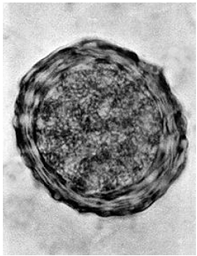

Em um exame parasitológico de fezes, foi realizado o método de sedimentação espontânea e encontrado o ovo ilustrado a seguir. Este ovo pertence a qual parasito?